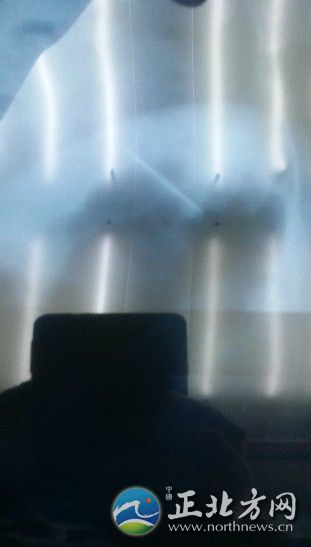

缝衣针离心脏很近

因为不敢相信检查结果,阿拉腾花又多次到其他的医院进行了检查,结果均让人失望,体内存在5枚缝衣针是不争的事实。医生还发现,这5枚缝衣针中,有1枚距离心脏非常近,只有几厘米,这枚针严重威胁着阿拉腾花的生命,急需手术取出。